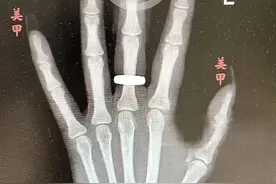

俗话说:“手是人的第二张脸。”生活中,很多女孩子喜欢做美甲,让“第二张脸”闪亮起来,但我们的指甲主要是为了保护富含神经的指尖免于受伤,过度的美甲反而会使我们的指甲受伤。2月17日,怀化市第二人民医院靖州院区急诊科接诊了一位美甲后指甲盖脱落的患者。